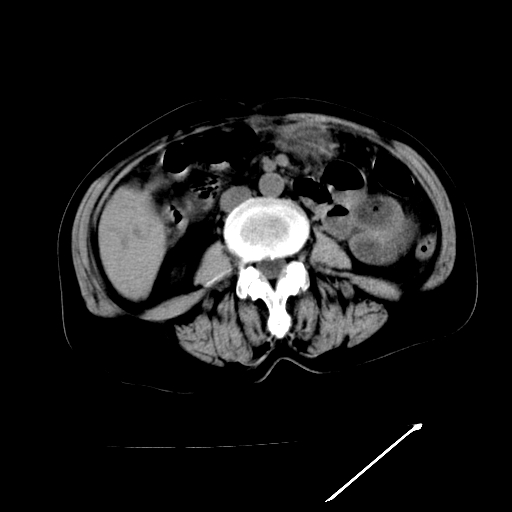

以下是引用随光逐影在2009-4-7 8:21:00的发言:[br]肝内外胆管多发性结石并肝内外胆管扩张;胆系感染。